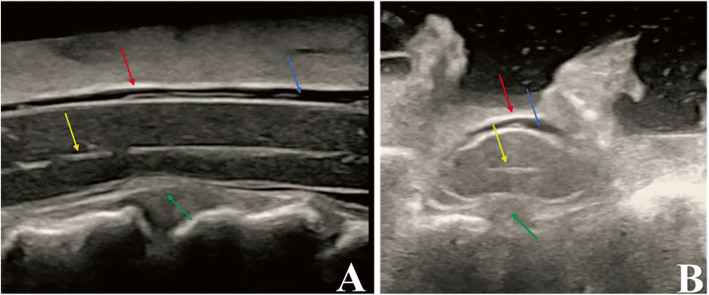

Fig. 1.

The anatomy of the spinal cord observed by intraoperative ultrasound. a) Midsagittal image, (b) Axial image. Red arrows indicate the spinal dura mater, yellow arrows indicate the central canal, blue arrows indicate the subarachnoid space and green arrows indicate the cervical disc